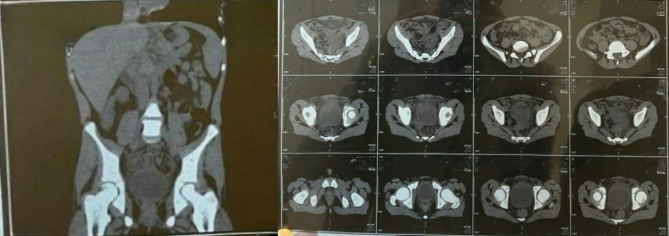

Case presentation: An 11-year-old boy presented with persistent suprapubic pain and dysuria for one week. Initial urine analysis revealed turbid urine with high numbers of red blood cells, leading to a diagnosis of urinary tract infection (UTI), and antibiotic treatment was initiated. However, the patient's symptoms persisted, with worsening clinical signs. A complete blood count revealed leukocytosis with neutrophilia, suggesting the need for further evaluation. A non contrast computed tomography (CT) scan revealed a thickened, blind-ended structure in the midline lower abdomen with gas, extensive fat stranding, and associated mesenteric lymphadenopathy, suggestive of perforated Meckel's diverticulum. The patient underwent laparoscopic exploration, which revealed an abscess caused by perforated Meckel's diverticulum adherent to the urinary bladder. Diverticulectomy and incidental appendectomy were performed via a stapling device. Pathology confirmed a perforation of Meckel's diverticulum with serofibrinous peritonitis and follicular appendicitis. The postoperative course was uneventful, with the patient resuming full oral intake by the fifth day and being discharged in stable condition.